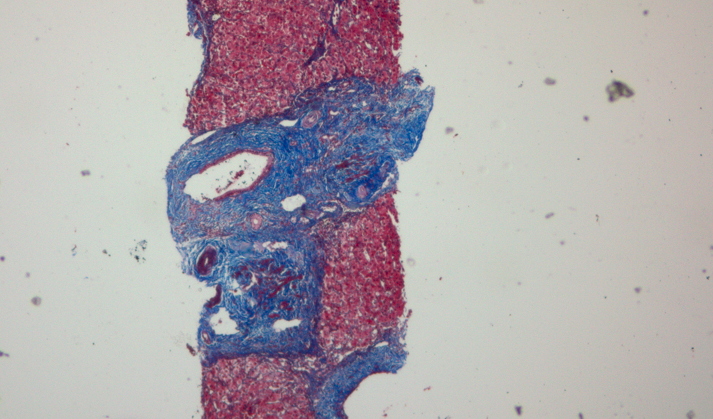

病理解读:肝组织全下叶炎症,轻中度界面炎,形成桥接样坏死带,炎症细胞浸润以淋巴-浆细胞为主,胆管形态结构基本正常,少数胆管有淋巴细胞嵌入。汇管区扩大,被大量纤维填充,纤维间隔形成。炎症及纤维化评分:G2S2。支持自身免疫性肝炎诊断。